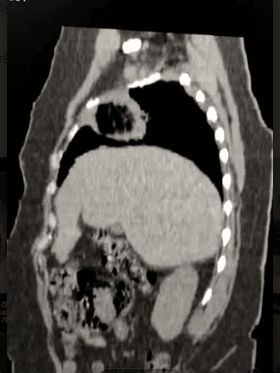

Figura 3 Tac de torax corte sagital y coronal Lesión en lóbulo Superior Derecho, cavitada de paredes gruesas.